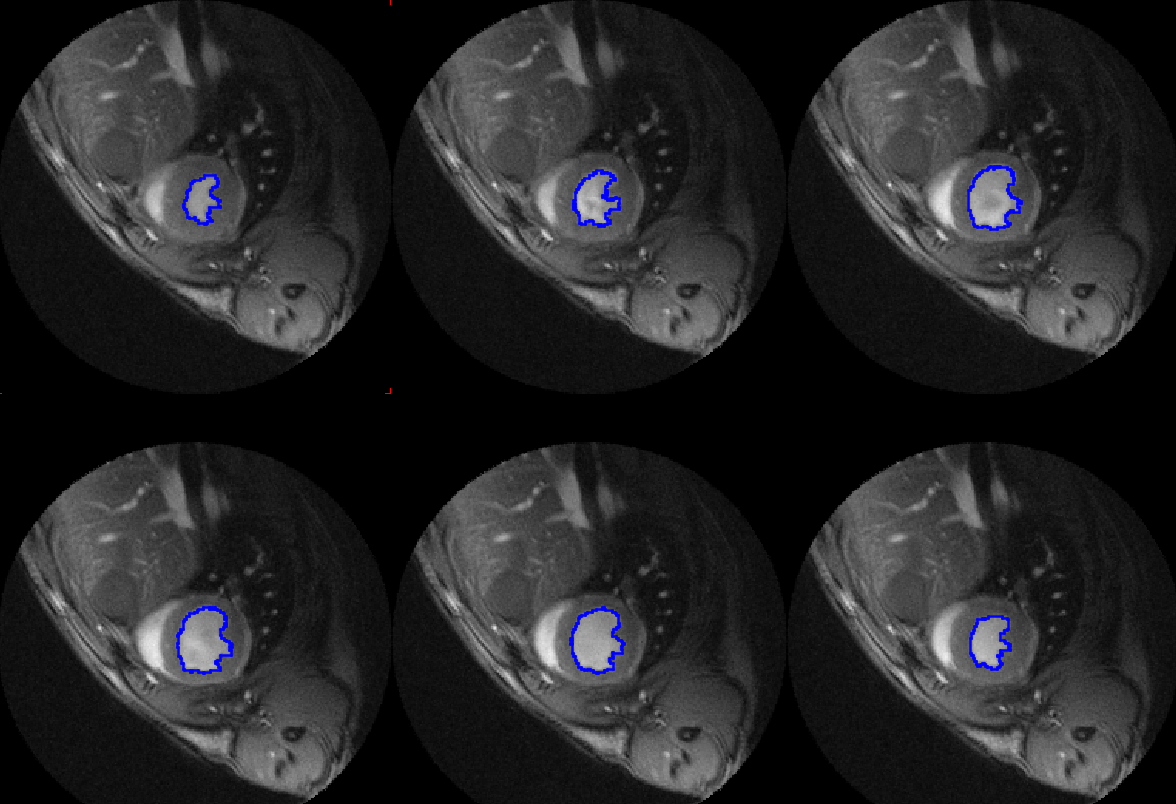

Leggi di piùPCARDP Cardiac PET Analysis

PCARDM Cardiac MR Analysis

P3D Extended Image Rendering